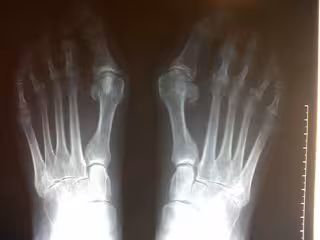

Entre el 40 y el 80 por ciento de las mujeres utilizan tacones altos de manera cotidiana, lo que las expone a padecer a la larga de juanetes o 'hallux valgus', una deformidad crónica en los huesos del pie, que puede estar provocada por el uso reiterado de zapatos con un tacón superior a 3 centímetros.

En el estudio se analizaron 80 mujeres sin deformidades previas en el pie, y se las midió con y sin zapatos de tacón pero sin puntera estrecha. Así, se observó que los dos huesos que se desvían en el HAV, esto es, la falange proximal del hallux y el primer metatarsiano, lo hacían según se aumentaba la altura de los tacones.

Cuando se quitaban el tacón, el dedo volvía a la normalidad, por tanto, "con este estudio hemos demostrado que usar tacones altos (a partir de 3 centímetros), de manera continua, provocará la pequeña desviación de los huesos y a la larga, de manera acumulativa, se instaurará la deformidad ósea", concluye la investigación, en la que colaboraron los doctores Ricardo Becerro y Marta Elena Losa.

Los juanetes, que afecta a casi un 60 por ciento de las mujeres mayores de 50 años, "son causa frecuente de dolor en el pie y provocan alteraciones en la pisada que pueden conllevar otro tipo de problemas secundarios, afectando incluso a la columna lumbar", afirma el doctor Sánchez-Gómez.